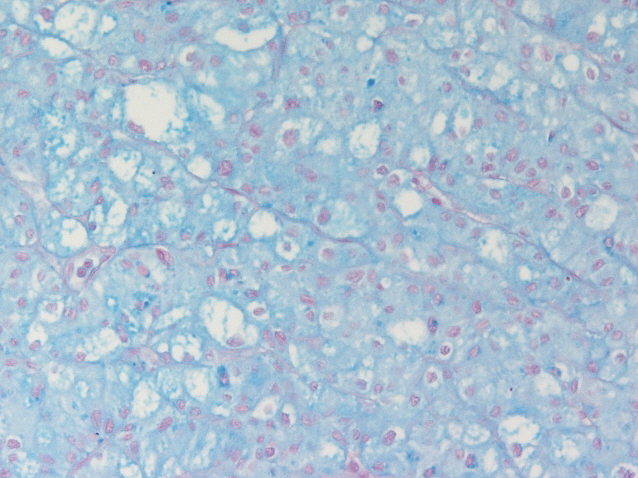

Consensus grade: Chromophobe RCC

SDH-deficient renal cell cancer if colloidal iron was negative

H&E not typical of eosinophilic chromophobe. Have seen Hale's positive cases like this that do not have chromosomal abnormilities typical of chromophobe.

another chromophob, I guess very classic, could maybe become a consensus case